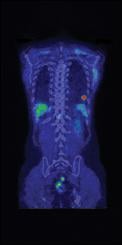

To recognize the advances in the field of nuclear and molecular imaging, as well as the professionals who carry out these procedures, the Society of Nuclear Medicine and Molecular Imaging (SNMMI) and the SNMMI Technologist Section (SNMMI-TS) celebrate Nuclear Medicine and Molecular Imaging Week, Oct. 6-12, 2013. The theme of this year’s Nuclear Medicine and Molecular Imaging Week is “Molecular Imaging: The Future … Delivered.”